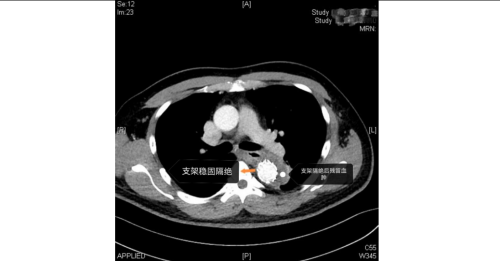

手术室内,患者血压一度飙至惊人的320/150mmHg,循环濒临崩溃!麻醉团队全力稳定循环。在患者下肢几乎无法触摸到脉搏的极端条件下,外周血管介入科主任赵扬程及团队迎难而上,凭借精湛技术,精准置入支架,成功封堵主动脉内膜巨大破口,并精细重建了主动脉弓部受累的重要分支血管,恢复关键血流。这场持续近3小时的手术每一步都高风险且高度紧张,如同在死神面前进行“拆弹”。最终,这颗“血管炸弹”被成功拆除。